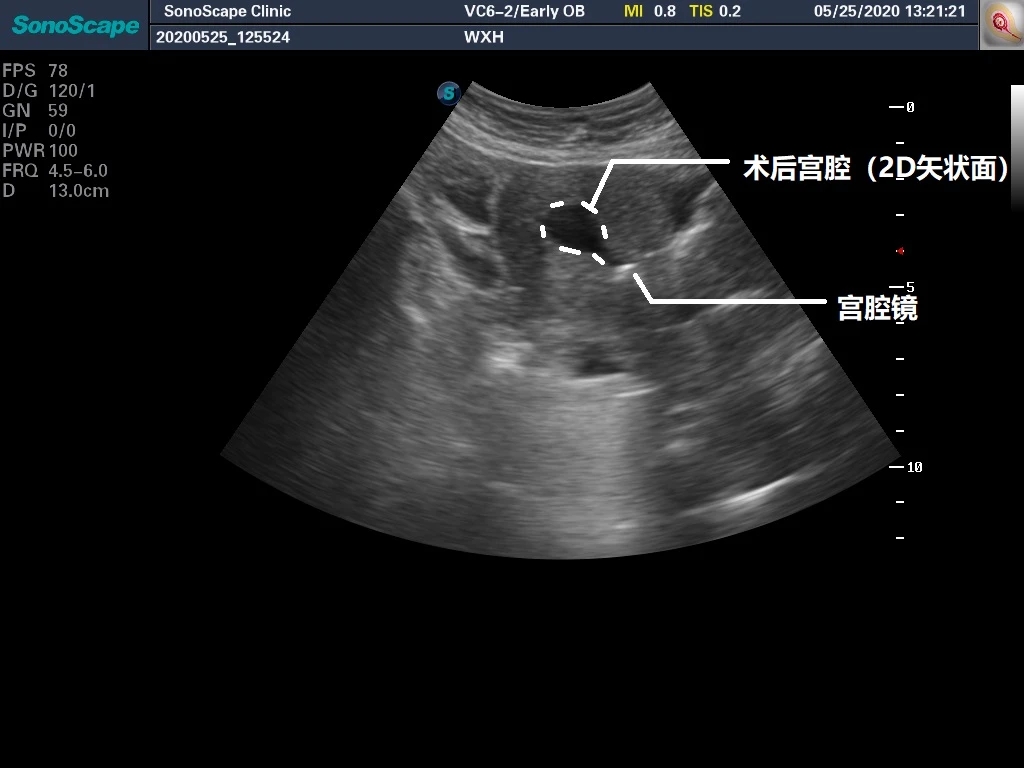

本例患者是“既往胎停后继发不孕,试管婴儿助孕后再次胎停后2个月月经不复潮”来诊,使用孕激素后月经有来潮,但月经量显著减少,彩超检查发现内膜薄。术前外院彩超没有电子版,在这里直接提供一份手术开始前的超声所见。

在上面这个图片中,我们可以大约看到子宫的轮廓以及微弱的内膜回声,标注呈现如下图:

在这个超声上面,悍然出现两个“眼睛”,彩超见原“内膜仅存之处”呈现一个被膨宫液撑起的腔,而与宫腔镜末端紧邻之处则也呈现出一个腔隙,那个就是我们宫腔镜下所看到的小空间。将两个腔隙之间的部分打通,即可恢复宫腔结构。上图进行辅助线标记如下: